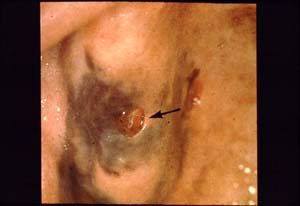

Malignant Melanoma (Melanin Producing Cell Tumor)

Photo 3